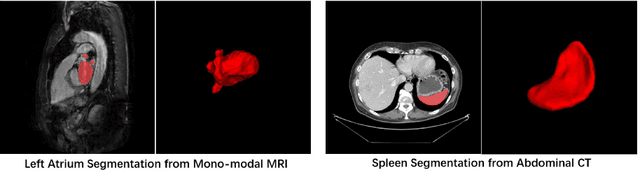

Abstract:Medical image segmentation is a fundamental and critical step in many clinical approaches. Semi-supervised learning has been widely applied to medical image segmentation tasks since it alleviates the heavy burden of acquiring expert-examined annotations and takes the advantage of unlabeled data which is much easier to acquire. Although consistency learning has been proven to be an effective approach by enforcing an invariance of predictions under different distributions, existing approaches cannot make full use of region-level shape constraint and boundary-level distance information from unlabeled data. In this paper, we propose a novel uncertainty-guided mutual consistency learning framework to effectively exploit unlabeled data by integrating intra-task consistency learning from up-to-date predictions for self-ensembling and cross-task consistency learning from task-level regularization to exploit geometric shape information. The framework is guided by the estimated segmentation uncertainty of models to select out relatively certain predictions for consistency learning, so as to effectively exploit more reliable information from unlabeled data. We extensively validate our proposed method on two publicly available benchmark datasets: Left Atrium Segmentation (LA) dataset and Brain Tumor Segmentation (BraTS) dataset. Experimental results demonstrate that our method achieves performance gains by leveraging unlabeled data and outperforms existing semi-supervised segmentation methods.

Abstract:Consistency training has proven to be an advanced semi-supervised framework and achieved promising results in medical image segmentation tasks through enforcing an invariance of the predictions over different views of the inputs. However, with the iterative updating of model parameters, the models would tend to reach a coupled state and eventually lose the ability to exploit unlabeled data. To address the issue, we present a novel semi-supervised segmentation model based on parameter decoupling strategy to encourage consistent predictions from diverse views. Specifically, we first adopt a two-branch network to simultaneously produce predictions for each image. During the training process, we decouple the two prediction branch parameters by quadratic cosine distance to construct different views in latent space. Based on this, the feature extractor is constrained to encourage the consistency of probability maps generated by classifiers under diversified features. In the overall training process, the parameters of feature extractor and classifiers are updated alternately by consistency regularization operation and decoupling operation to gradually improve the generalization performance of the model. Our method has achieved a competitive result over the state-of-the-art semi-supervised methods on the Atrial Segmentation Challenge dataset, demonstrating the effectiveness of our framework. Code is available at https://github.com/BX0903/PDC.

Abstract:The success of deep learning methods in medical image segmentation tasks usually requires a large amount of labeled data. However, obtaining reliable annotations is expensive and time-consuming. Semi-supervised learning has attracted much attention in medical image segmentation by taking the advantage of unlabeled data which is much easier to acquire. In this paper, we propose a novel dual-task mutual learning framework for semi-supervised medical image segmentation. Our framework can be formulated as an integration of two individual segmentation networks based on two tasks: learning region-based shape constraint and learning boundary-based surface mismatch. Different from the one-way transfer between teacher and student networks, an ensemble of dual-task students can learn collaboratively and implicitly explore useful knowledge from each other during the training process. By jointly learning the segmentation probability maps and signed distance maps of targets, our framework can enforce the geometric shape constraint and learn more reliable information. Experimental results demonstrate that our method achieves performance gains by leveraging unlabeled data and outperforms the state-of-the-art semi-supervised segmentation methods.